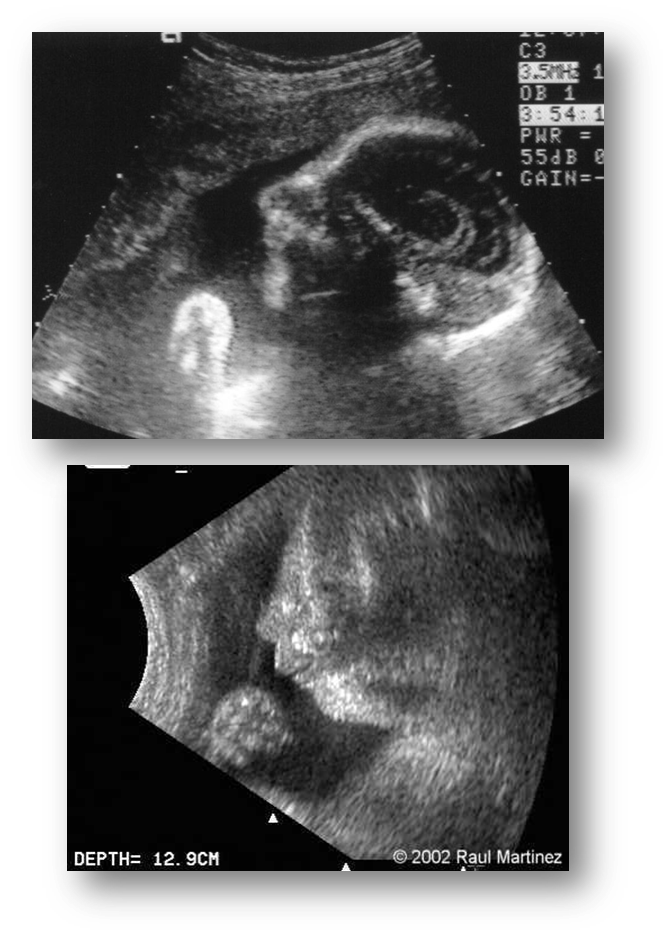

What is Micrognathia?

Small/depressed chin

Seen in profile

What is associated with Micrognathia?

Chromosomal anomalies

Trisomy 18 & Triploidy

Skeletal dysplasia’s

Primary mandibular disorders

Micrognathia

Where is the fetal mandible(chin) seen best?

In a profile view

What are these images showing?